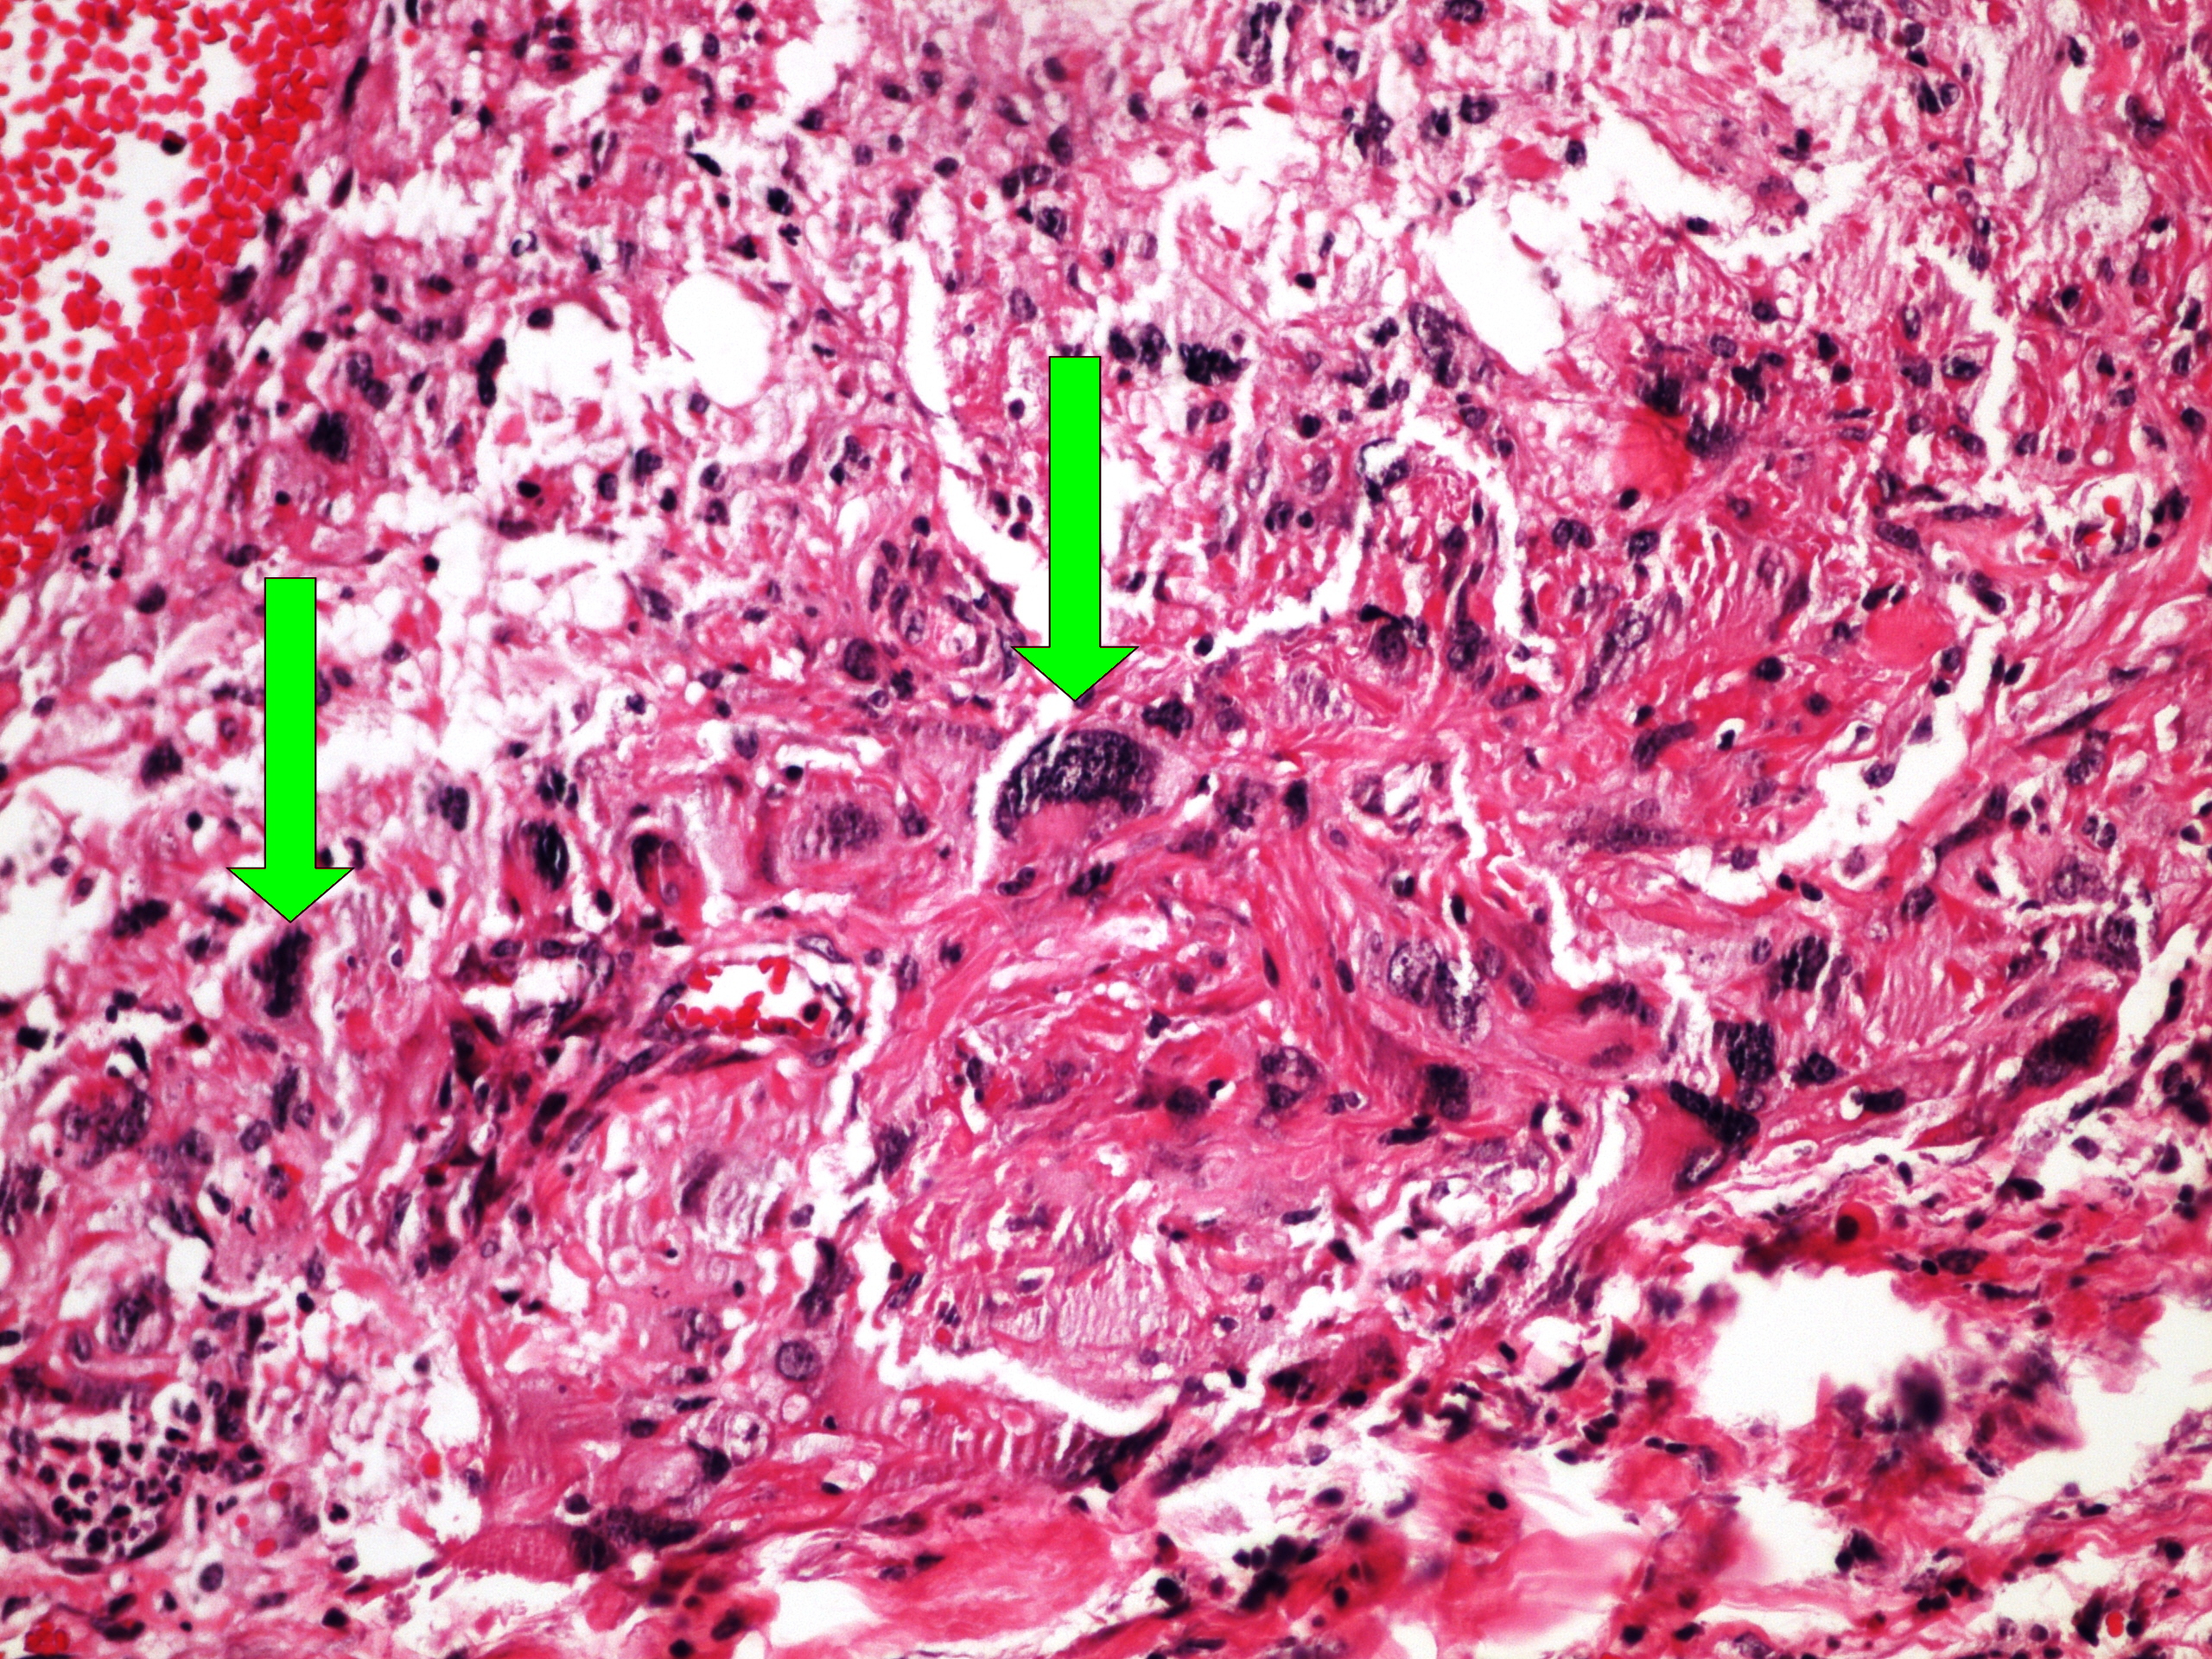

Preparát č.1 a č.2 - kavernósní hemangiom jater

Struktury

- hemangiom

- jaterní parenchym

- blandní epitelie - stěna hemangiomu